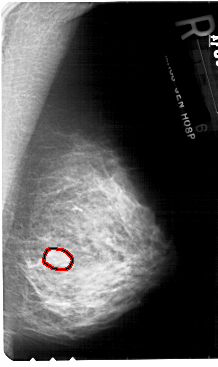

FILE: A_1781_1.RIGHT_MLO.OVERLAY

TOTAL_ABNORMALITIES 1

ABNORMALITY 1

LESION_TYPE MASS SHAPE OVAL MARGINS ILL_DEFINED

ASSESSMENT 4

SUBTLETY 3

PATHOLOGY BENIGN

TOTAL_OUTLINES 1

BOUNDARY